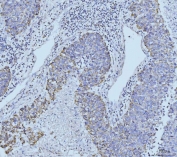

IHC staining of FFPE human colonic adenocarcinoma tissue with ETFA antibody. HIER: boil tissue sections in pH8 EDTA for 20 min and allow to cool before testing.